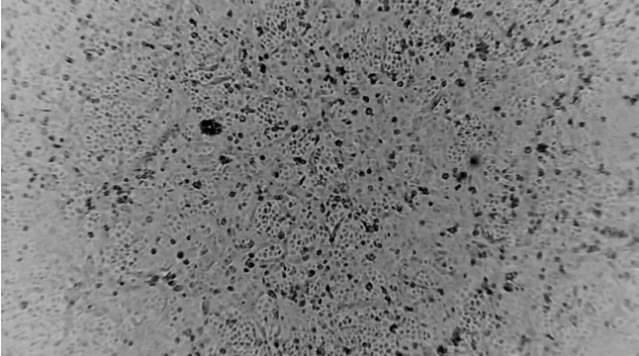

▲ 호주의 한 연구소에서 신종 코로나(우한 폐렴) 바이러스를 복제하는 데 성공했다. 로이터=연합뉴스 제공

호주 한 연구소에서 '우한 폐렴' 원인으로 지목되는 신종 코로나바이러스를 실험실에서 재생산(복제)하는 것에 성공했다.

호주 멜버른대의 피터 도허티 감염·면역 연구소(이하 도허티 연구소) 연구진은 지난 24일 신종 코로나바이러스 감염자로부터 바이러스를 얻어 이날 추가로 배양해냈다고 로이터통신이 호주 ABC방송을 인용해 29일 보도했다. 이는 중국 밖 연구실에서 신종 코로나바이러스가 재생산된 최초 사례다. 연구진은 배양한 바이러스 샘플을 세계보건기구(WHO), 전 세계 연구소와 공유하겠다고 했다.

도허티 연구소의 부소장 마이크 캐턴은 ABC방송에 이 샘플들은 앞으로 백신 개발 작업에 중대한 역할을 할 것이라고 기대감을 드러났다. 샘플은 신종 코로나바이러스에 감염됐지만 증상은 나타나지 않는 사람들을 가려내는 항체 검사를 개발하는 데에도 사용될 계획이다.